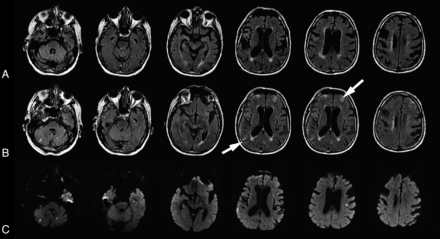

We found HARM in 9 patients (47%); of these, 7 (78%) also had DWI lesions (Table). Most patients had mild/moderate HARM, and only 2 (both in group 1) had severe sulcal or background HARM (Figs 2 and 3). There were more than twice as many patients with HARM in group 1 than in group 2 (66.7% versus 30%; P = .18). The proportion of patients with HARM was similar in patients who had on- versus off-pump procedures (38% versus 50%; P = 1.0).

A 74-year-old man who underwent off-pump CABG. A, Baseline FLAIR obtained before surgery. B, Postgadolinium scan. Gadolinium was administered 20 hours after surgery, and 3T MR imaging was performed 20 hours later. Postgadolinium FLAIR shows enhancement throughout the subarachnoid space (severe sulcal and background HARM). The CSF in the ventricles appears gray (mild/moderate ventricular HARM). Gadolinium enhancement is also seen in the eye. C, DWI obtained after surgery. Patient had 4 DWI lesions.

An 86-year-old man who underwent CABG. A, Baseline FLAIR performed before surgery. B, Postgadolinium FLAIR. Gadolinium was administered 23 hours after surgery, and the 1.5T MR imaging was obtained 27 hours later. Postgadolinium FLAIR shows bright enhancement in the right frontal and left parietal subarachnoid space (arrows, severe sulcal HARM). C, Postoperative DWI. The patient had 6 DWI lesions.